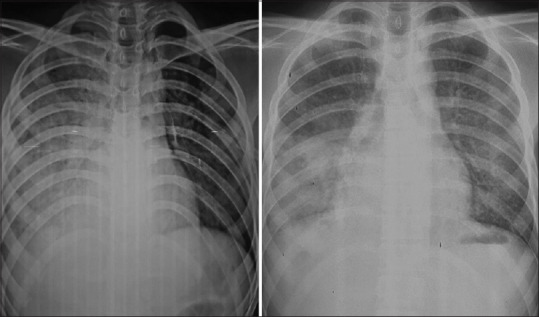

Abstract Image